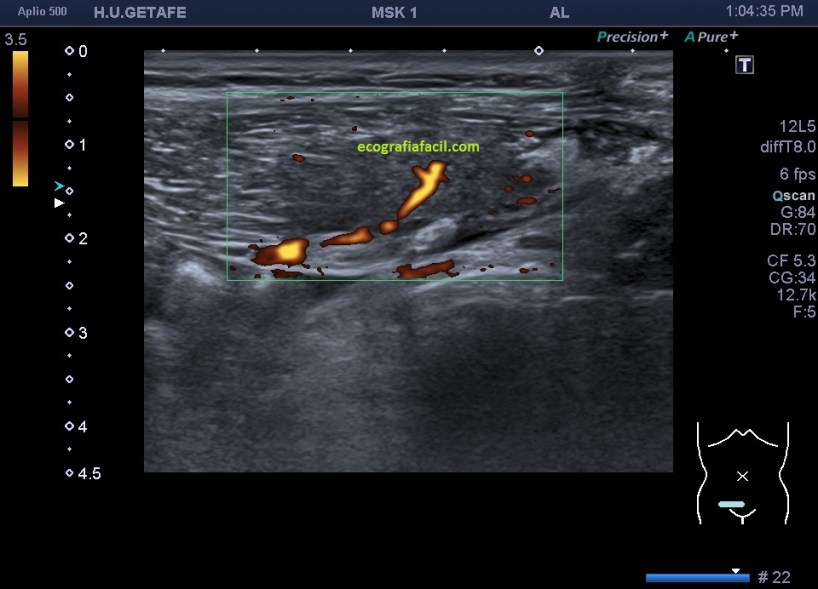

El estudio doppler arroja el hallazgo de un vaso importante que está alcanzando y nutriendo la región afectada. Puedes observar como es un vaso de alto flujo y de buen tamaño. No pude demostrar vascularización perimetral de la lesión.